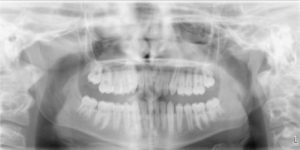

A 12.4 year old caucasian male presents with a chief complaint of “underbite and crooked teeth”